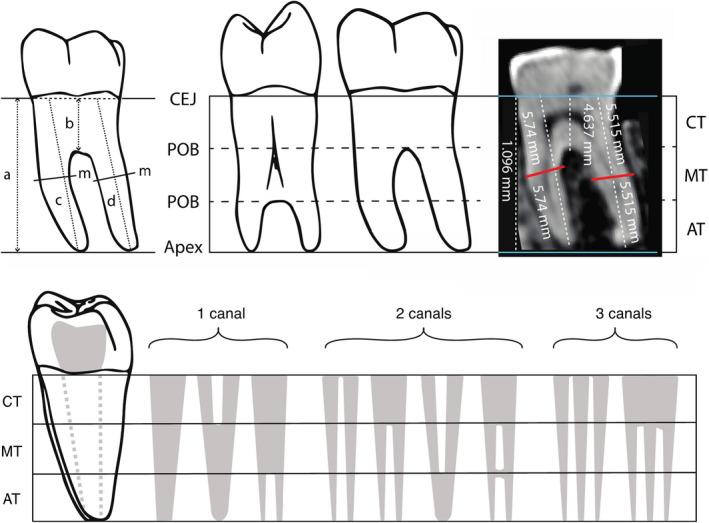

Patterns of variation in canal and root number in human post-canine teeth.

Descriptive morphology of tooth roots traditionally focuses on number of canals and roots. However, how or if canal and root number are related is poorly understood. While it is often assumed that canal number is concomitant with root number and morphology, in practice canal number and morphology do not always covary with external root features. To investigate the relationship between canal and root number, fully developed, adult post-canine teeth were examined and quantified from computerized tomography scans from a global sample of 945 modern humans. We tested the hypotheses that root and canal number do not follow a 1:1 ratio, that canal to root ratios differ between teeth, and that canal to root ratios differ across major human geographical groups. Results indicate that not only is root number dependent on canal number, but that this relationship becomes more variable as canal number increases, varies between individual teeth and by major geographical group, and changes as these groups increase in geographical distance from Sub-Saharan Africa. These results show that the ratio of canal number to root number is an important indicator of variation in dental phenotypes.